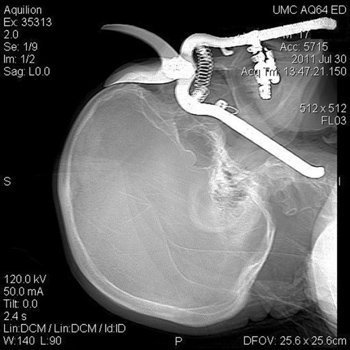

Người đàn ông Mỹ không may đã bị ngã và cắm thẳng mặt vào một chiếc kìm.